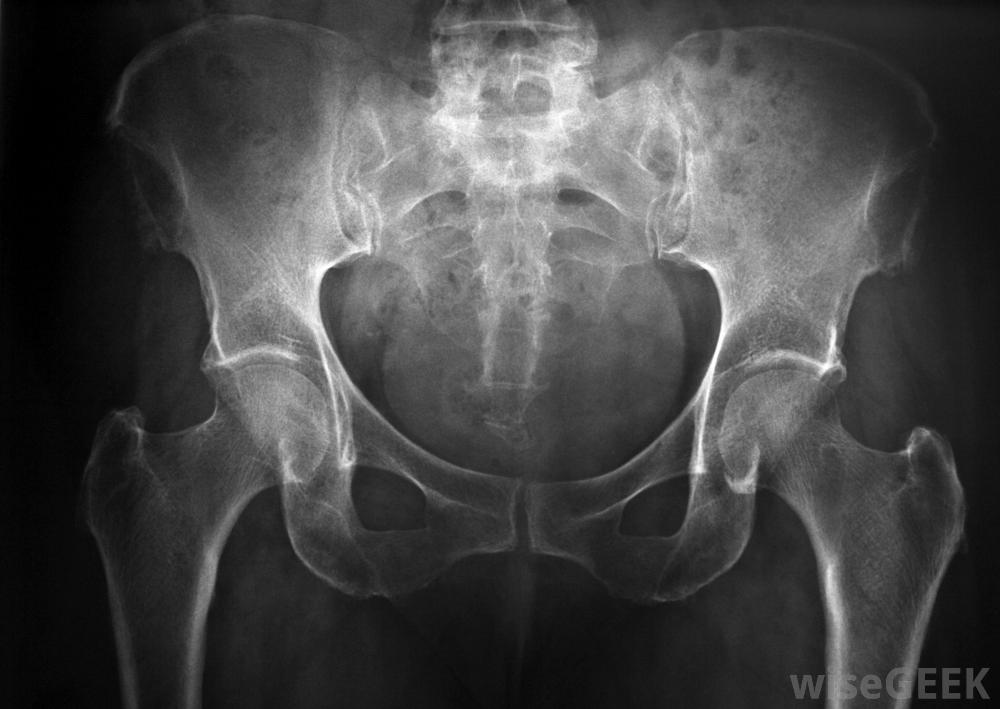

用x光检查输尿管支架的放置情况。

病人在支架置入期间接受全身麻醉泌尿科医生通过将一个称为膀胱镜的小伸缩管插入尿道并插入膀胱来安装输尿管支架。然后将支架穿过膀胱镜,放入输尿管和肾脏。通过X光检查确定支架是否正确放置。如果没有,当肾结石被困在输尿管中时,可以使用输尿管支架。